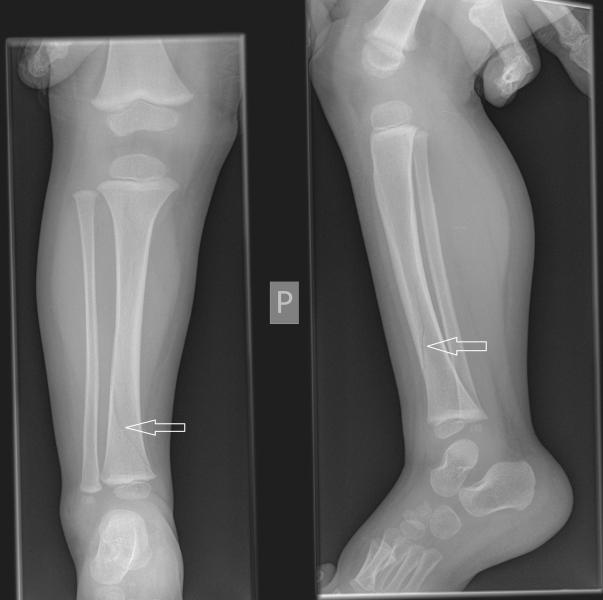

Przypadek 10: 2-letni chłopiec, upadł i gwałtownie skręcił prawą nogę. Obecnie skarży się na ból okolicy stawu skokowego, nie chce chodzić.

Rozpoznanie: Spiralne złamanie dystalnego odcinka prawej kości piszczelowej, bez przemieszczenia.